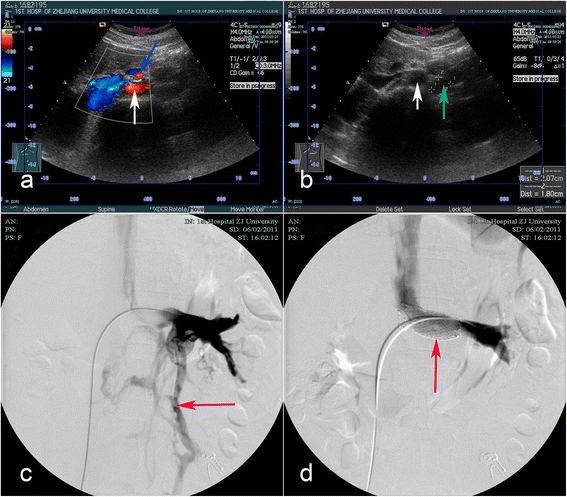

Case presentation: A 30-year-old female was diagnosed with nutcracker syndrome for severe left flank pain. After failed conservative approach, she underwent endovascular stenting and subsequently developed recurrent symptom for stent migration one month postoperatively. She underwent successful extravascular stenting with complete symptom resolution.

Conclusion: The extravascular stenting is an alternative option after migration of left renal vein endovascular stenting. The computed tomographic imaging was closely correlated to therapeutic interventions and stent migration.